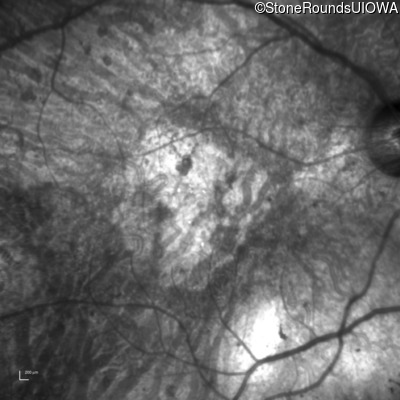

OD

OS

1/200 sc

Age at visit:

76 years